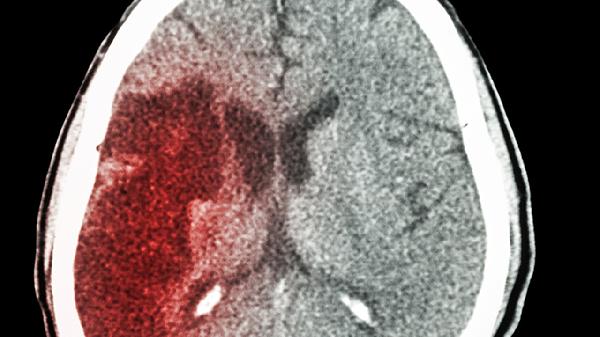

脑出血的急性期危险性更突出。脑血管破裂导致血液直接压迫脑组织,可能迅速引发颅内压升高、脑疝等致命并发症。发病后1个月内死亡率可超过30%,幸存者常遗留偏瘫、失语等后遗症。高血压性脑出血多见于基底节区,突发剧烈头痛伴呕吐是典型表现。动脉瘤破裂导致的蛛网膜下腔出血则易出现颈项强直和意识障碍。

出现突发偏瘫、言语不清或意识障碍时,应立即呼叫急救。确诊需通过头颅CT或MRI检查,脑出血可见高密度影,脑梗塞则显示低密度病灶。恢复期患者需坚持康复训练,控制血压血糖等基础疾病,定期神经科随访评估认知功能。饮食宜低盐低脂,避免情绪激动和过度劳累。